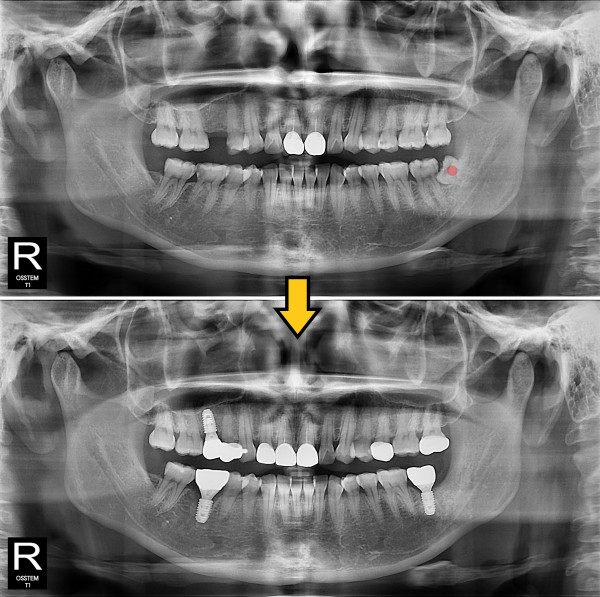

사랑니발치 30대/여성

ae27575af29d49719312fde5a1f0cca6_1764402680_8006.jpg